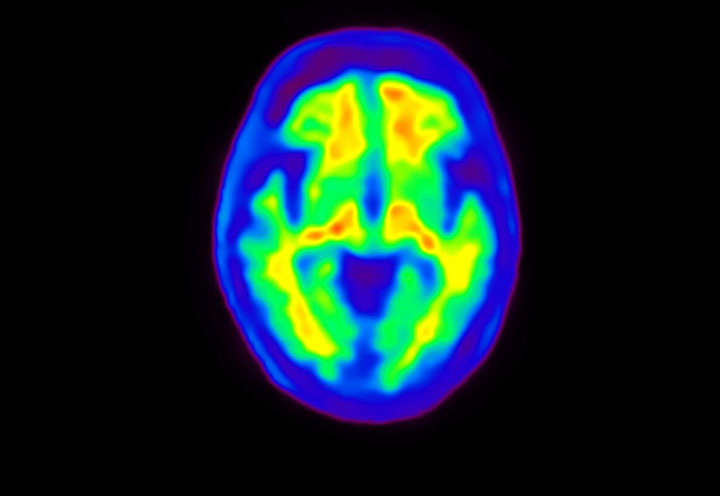

Head / Case4 : Amyloid

Axial

Courtesy : Kindai University Hospital

- Imaging protocol

- Injected dose: 3.21 MBq/kg, 18F-Flutemetamol

- Uptake time: 100 minutes

- Scan time: 20 minutes